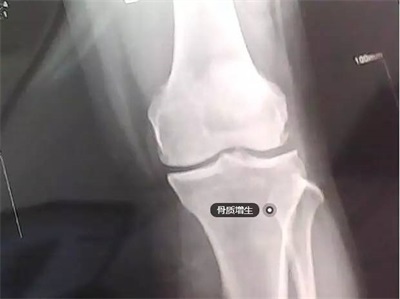

当然不是,骨刺,其实应该叫骨赘,也就是我们常说的骨质增生,常见于中老年人群,多形成于骨骼的边缘,呈新生的骨组织,在X光片上呈现底部宽、尖端细的突起样表现。